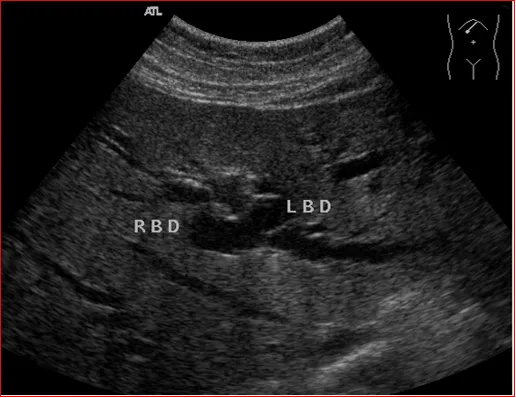

壶腹部低回声占位,胆总管扩张

壶腹部占位导致左右肝内胆管扩张